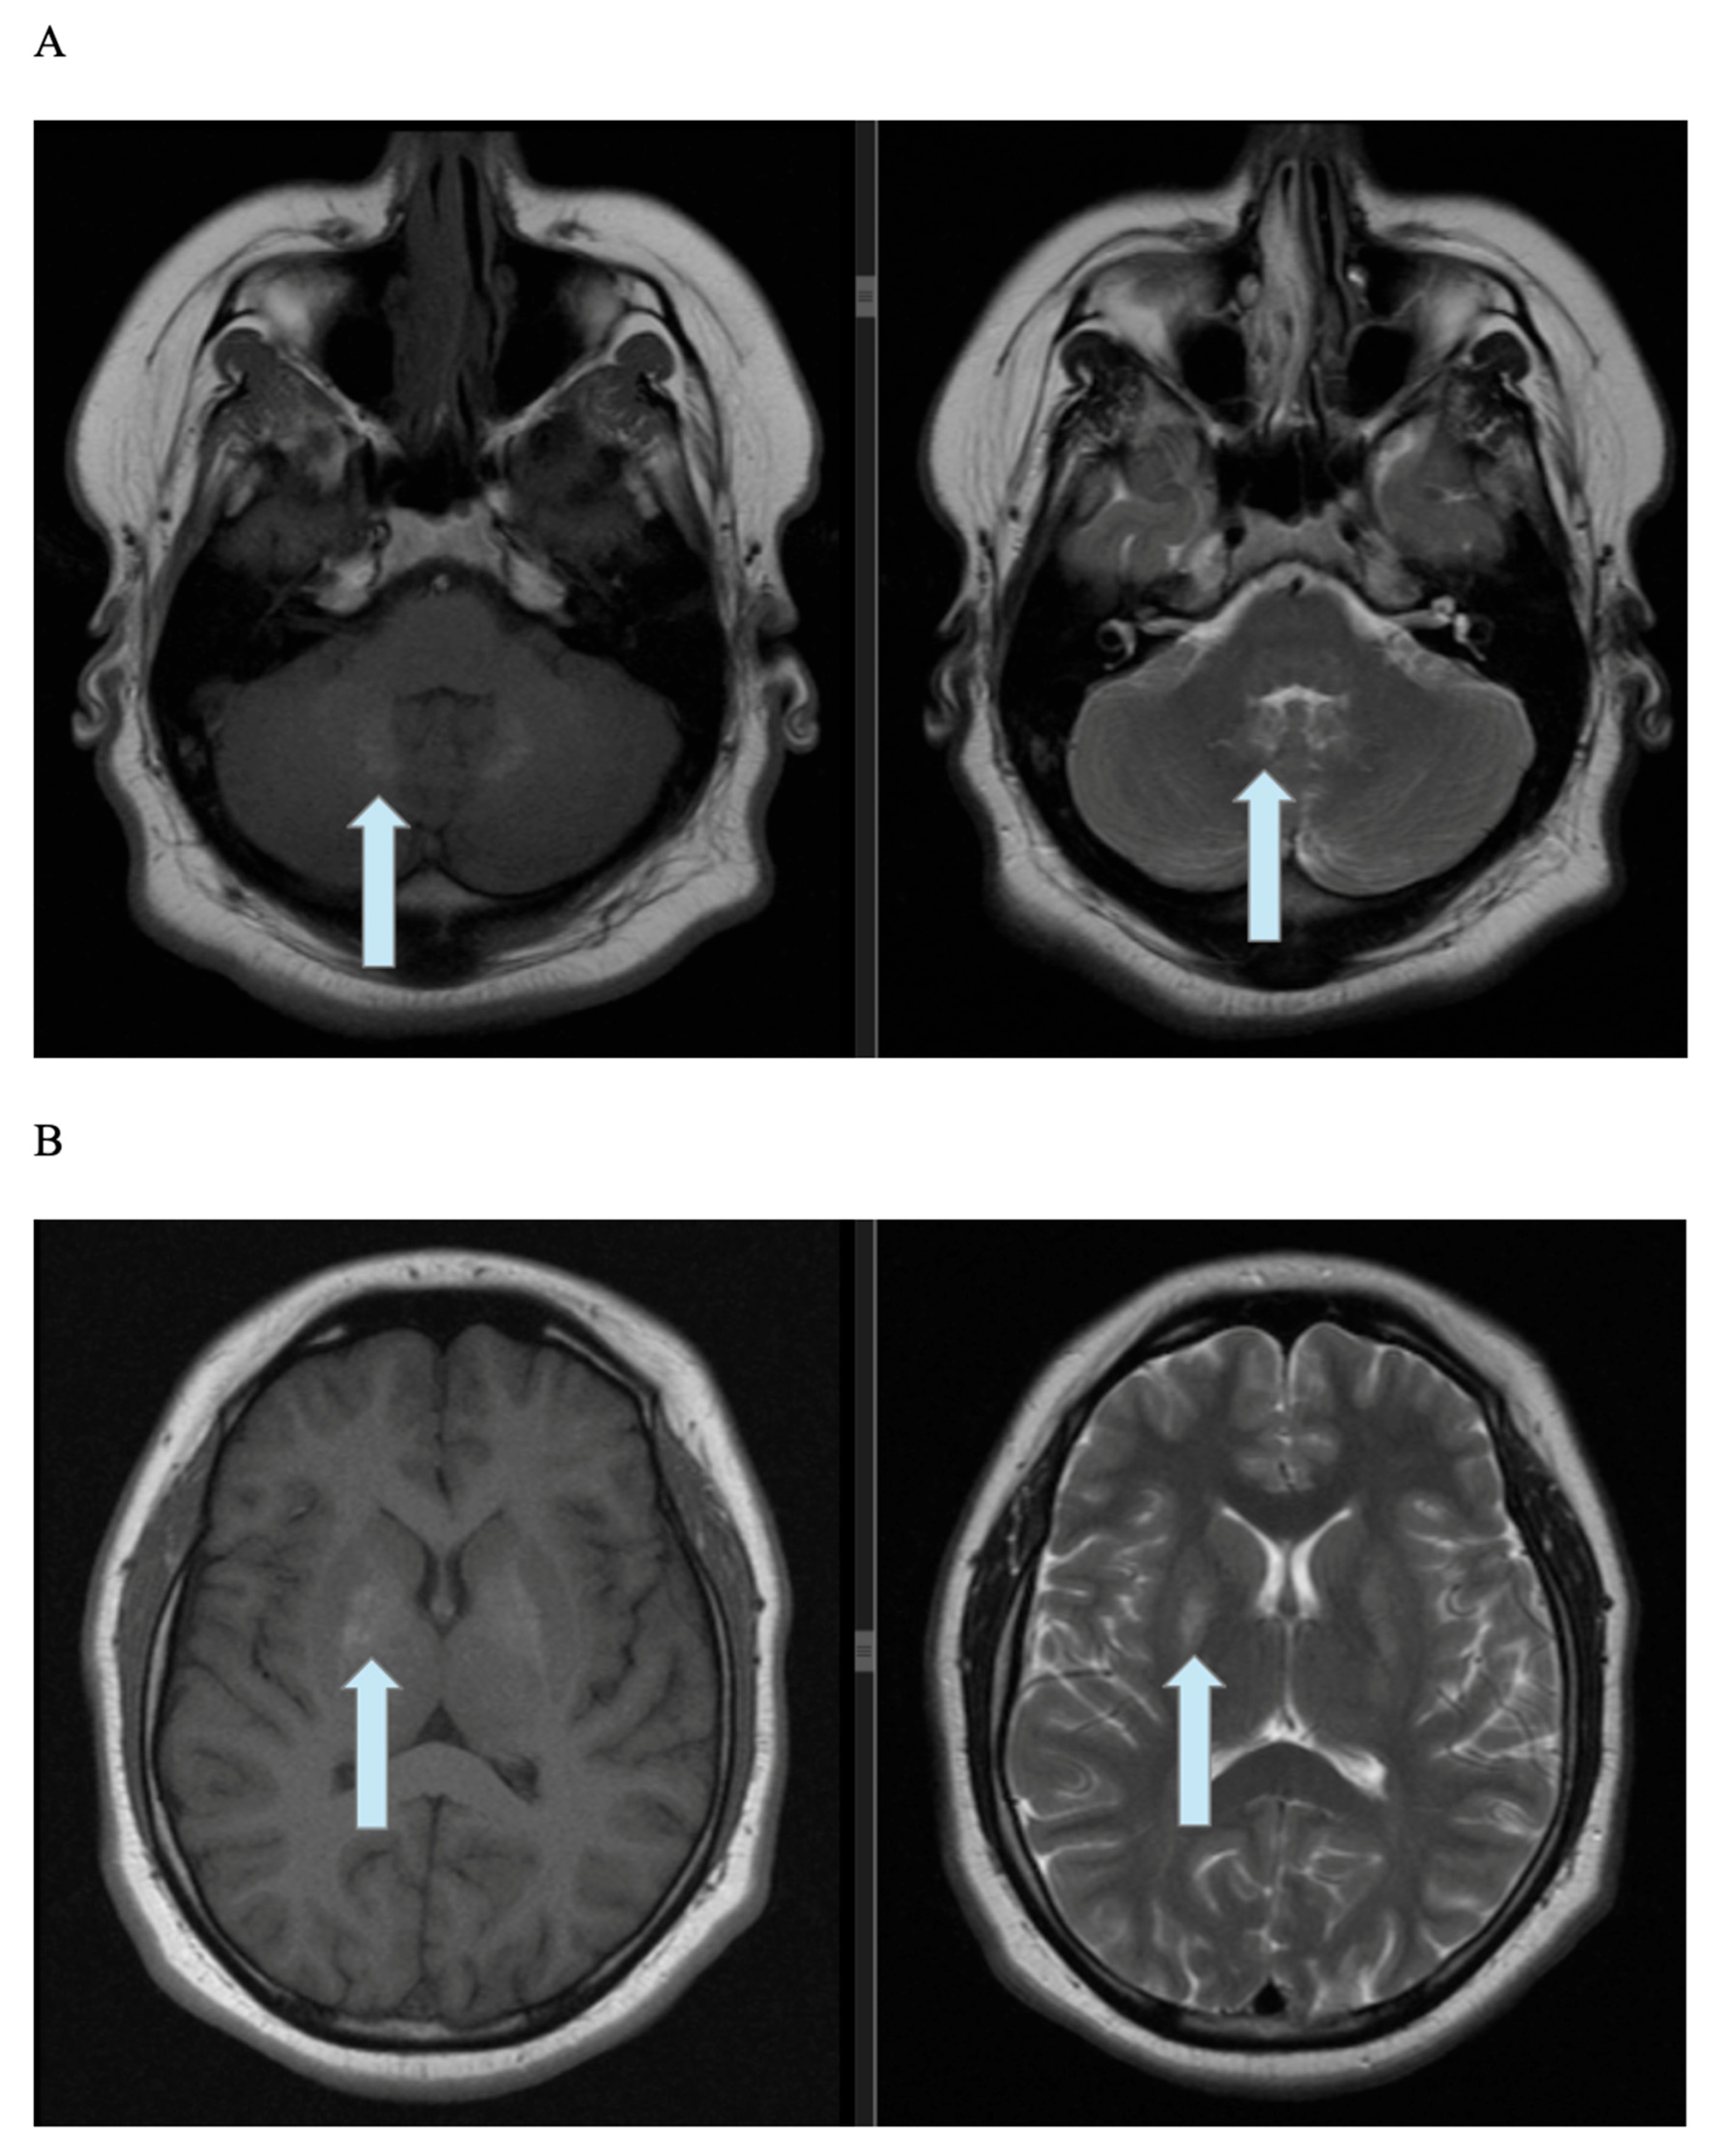

2.3. Imaging